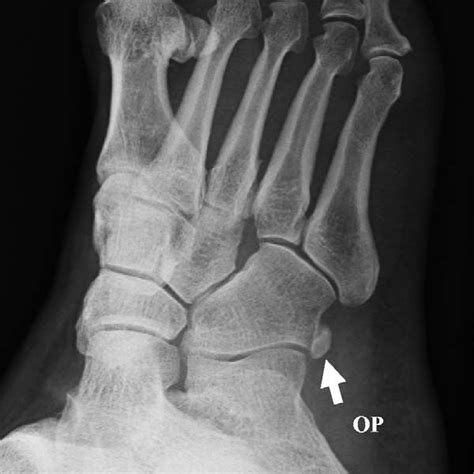

WebUna radiografía de pie puede ayudar a los médicos a encontrar la causa del dolor, la sensibilidad, la hinchazón o una deformidad. Permite ver si hay huesos rotos (fracturas). WebImagen lateral RX pie en carga. Galería . Radiología. Tags. Radiología. Pié. Tobillo. Articulación. Locomotor. Síguenos en las redes sociales Quiénes somos.. WebPDF | On May 1, 2019, David González-Martín published Radiología Pie y Tobillo | Find, read and cite all the research you need on ResearchGate WebPROYECCIONES RADIOLÓGICAS: PIE, DEDOS DEL PIE Y CALCÁNEO ANASTASIYA CHYCHETA, ÁLVARO GÓMEZ, CARLOS PÉREZ Y MARTA VENTURA. WebRadiología simple en traumatología Pie Las proyecciones radiológicas para evaluar traumatismos en el pie incluyen las Rxs de pie AP, oblicua y lateral. Si el dolor lo. WebAl tratarse de una radiografía de 2 proyecciones se obtendrán 2 imágenes. Se le llama pies de cargas porque las radiografías obtenidas son con el pie en posición lateral. En todo. WebLas radiografías del pie en una proyección directa a menudo se realizan para diagnosticar deformidades del pie plano, congénitas o adquiridas. A veces, la.

WebEl eje longitudinal del pie será paralelo al eje longitudinal del chasis y la incidencia en la mitad del pie que es la base del tercer metatarsiano. COLIMACIÓN: Observar la. WebRadiografía con carga en flexión para la detección precoz de artrosis de rodilla: mejorando el screening. Dr. Cristián Fontboté R., Dr. Fernando Nemtala U., Dr. Oscar Contreras O.,. Webla técnica descrita por Holly en la que el sujeto se coloca en posición sedente, el pie en dorsiflexión y una banda tracciona los dedos en sentido proximal, la des- ventaja reside.

WebAl tratarse de una radiografía de 2 proyecciones se obtendrán 2 imágenes. Se le llama pies de cargas porque las radiografías obtenidas son con el pie en posición lateral. En todo. WebLas radiografías del pie en una proyección directa a menudo se realizan para diagnosticar deformidades del pie plano, congénitas o adquiridas. A veces, la. WebPaciente en decubito lateral, apoyando la cara lateral del pie sobre el cassete.El haz de rayos es dirigido verticalmente al centro del tarso. Se realiza de forma.